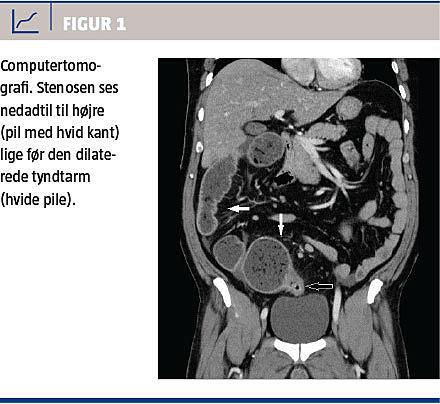

En 51-årig mand havde haft mb. Crohn siden 1997, hvor han fik foretaget total kolektomi med sekundær ileorektal anastomose. Han blev indlagt i 2012 med subileus, der blev behandlet med klyx. På en computertomografi sås der stenose i ileorektalanastomosen med præstenotisk dilatation (Figur 1). Under indlæggelsen blev der foretaget en sigmoideoskopi, som viste inflammatorisk sygdomsaktivitet i rectum samt relativ stenose ved ileorektalanastomosen. Man afstod i situationen fra endoskopisk dilatation, da patienten var i bedring, og der blev observeret fæces passere stenosen. Der blev til gengæld påbegyndt lokal antiinflammatorisk behandling og elektiv dilatation af stenosen.